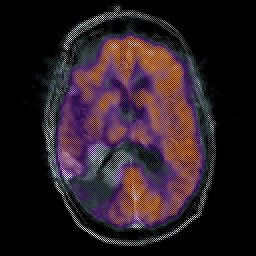

Glioma Overlay -- Slice #11

[Home][Help][Clinical] Slice 11